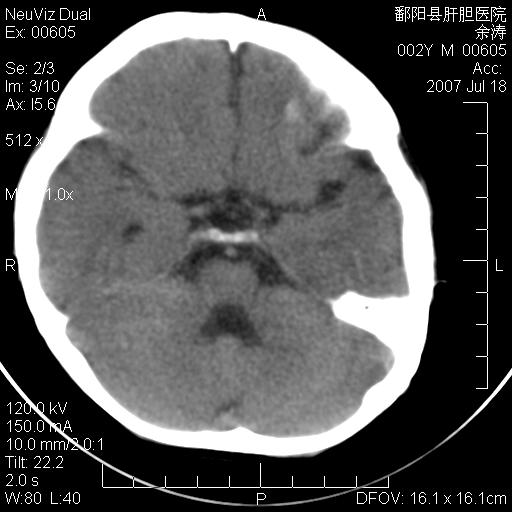

男性 2岁:平时智力障碍。外伤后行颅脑平扫。

3\\透明隔间腔

脑裂畸形;左侧脑脑萎缩;透明隔囊肿;血管畸形?

该病人应该还有胼胝体发育不全